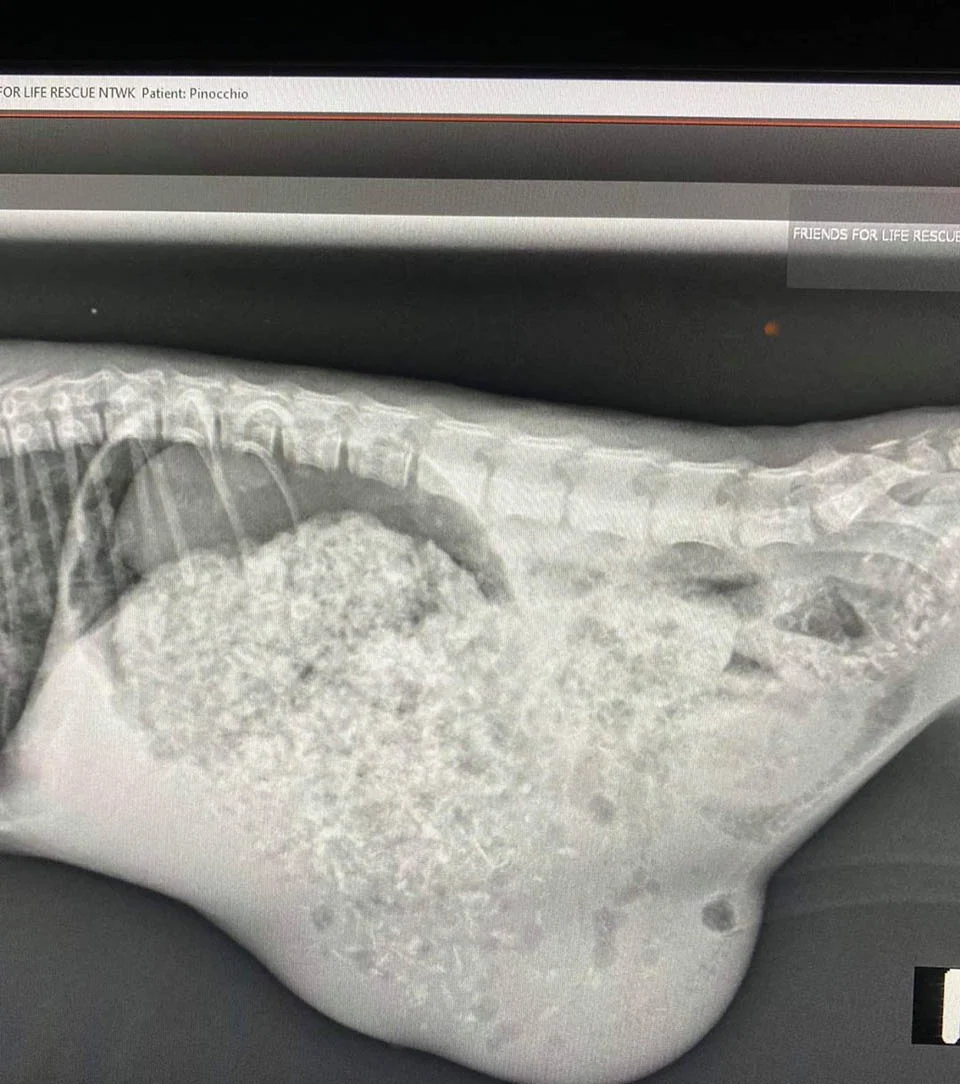

El pequeño Pinocchio Tenía una infección leve de las vías respiratorias superiores, una hernia umbilical, y la apariencia de su nariz y boca era diferente; dándole un aspecto particular.

El refugio Friends for Life Rescue Network se hizo cargo del pequeño gato. Allí descubrieron que su aspecto se debe a un defecto congénito que da a su mandíbula su apariencia desalineada.

Pinocchio es un gato muy feliz y mejora cada día, es muy activo y juguetón, pronto lo verá un especialista dental y un especialista neurológico para recibir toda la ayuda que requiere. El gatito parece saber que está en buenas manos y disfruta las visitas al veterinario.